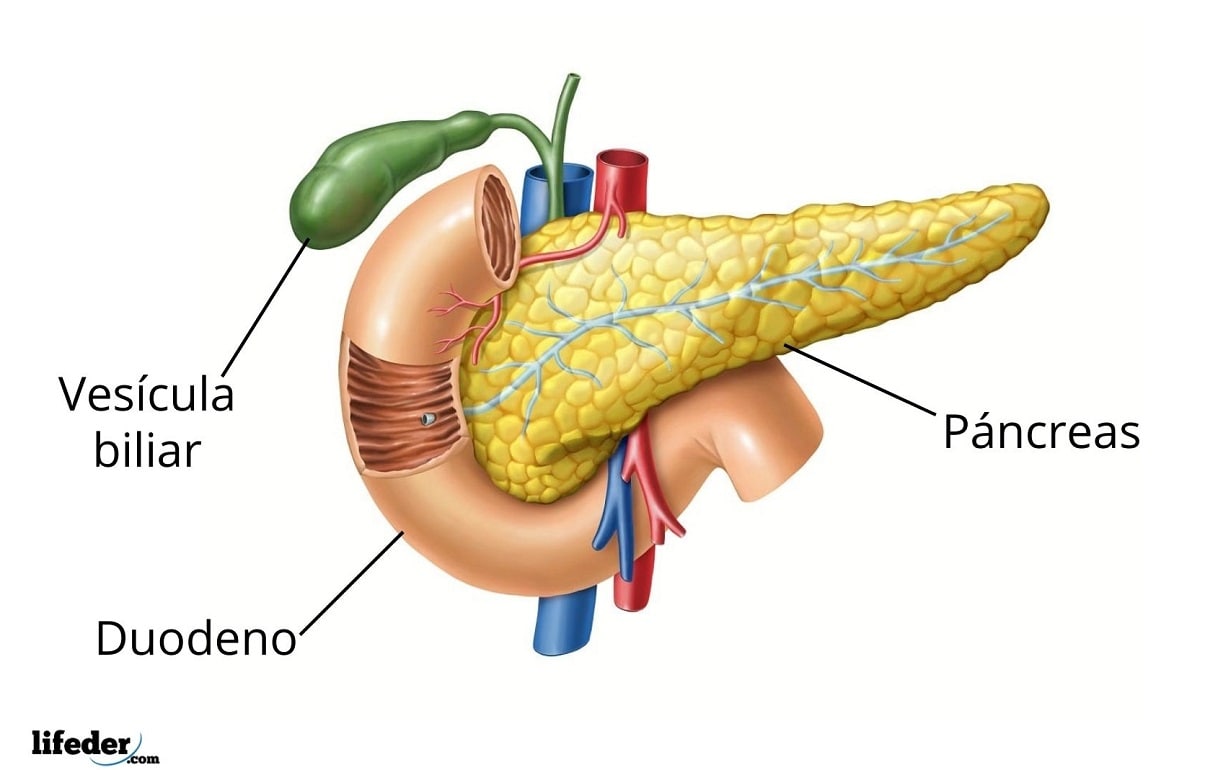

Este grupo de glándulas se caracteriza por secretar sus productos a través de conductos hacia la superficie (externa o interna) del epitelio donde se originan. La piel y el tracto digestivo, por ejemplo, reciben el sudor, la bilis y las enzimas digestivas de las glándulas sudoríparas, el hígado y el páncreas, correspondientemente.

– Glándulas serosas: secretan líquidos ricos en enzimas, un buen ejemplo de estas glándulas es el páncreas.

Es importante destacar que algunas glándulas del cuerpo humano son mixtas, lo que en otras palabras quiere decir que poseen porciones endocrinas y porciones exocrinas, ejemplo de las mismas son el páncreas, los testículos y los ovarios.

Respecto a las glándulas exocrinas, pueden señalarse algunas afecciones comunes al hígado o al páncreas, que son las conocidas “glándulas accesorias del sistema digestivo”. Tales enfermedades pueden o no ser de origen viral o pueden estar relacionadas con el estilo de vida de las personas que las padecen.

La porción exocrina del páncreas, que es la que forma parte de la función digestiva, también puede sufrir distintos desórdenes que afectan el funcionamiento normal de este órgano o glándula.

Si el páncreas no es capaz de secretar las enzimas digestivas que secreta (tripsinógeno, quimiotripsinógeno, procarboxipeptidasa, lipasa, amilasa, elastasa, ribonucleasa, desoxirribonucleasa), esto puede afectar seriamente la función gastrointestinal.